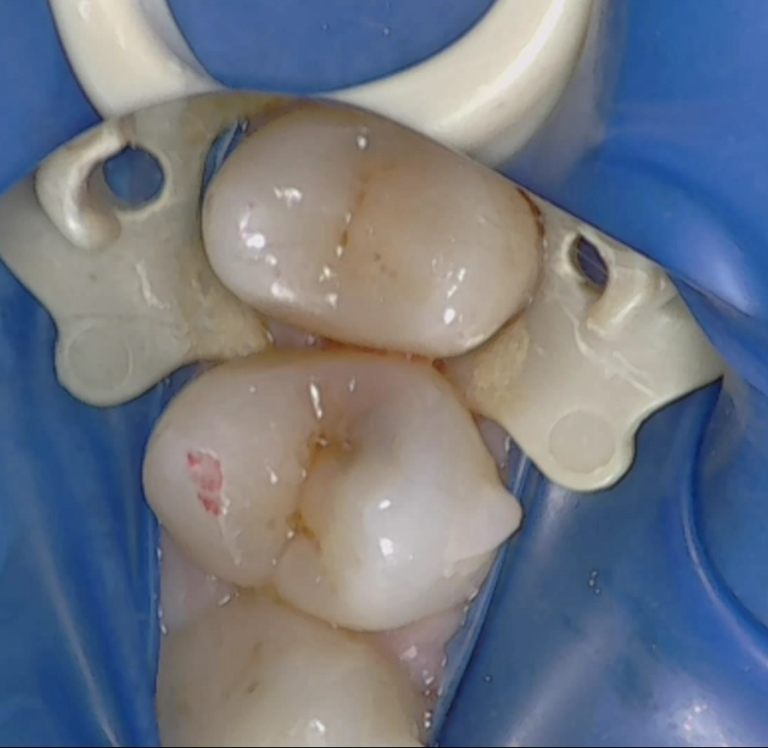

精密治療を希望されたので、歯科麻酔を行いラバーダム防湿を行なった。

歯質を削ってみると以下のように虫歯が広がっていた。

う蝕検知液を使用しつつ虫歯の部分のみを極力削るように心がけていきます。う蝕の除去後は下図のようになりましたが、虫歯の範囲も大きかったので歯髄を強くしてくれるお薬をおいてからコンポジットレジン修復で治療することになった。